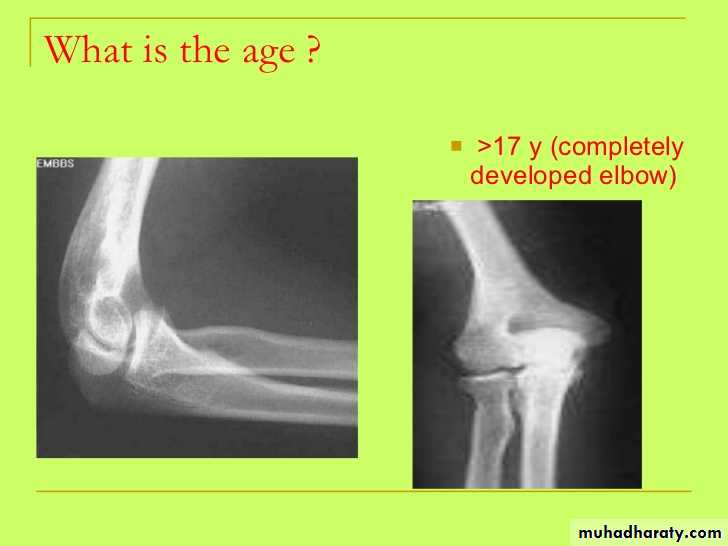

• تقدير العمر من العظام: يستطيع الطبيب ان يقدر العمر بدرجة لاباس بها من الدقة فيما بين الولادة وحتى سن 25 عاما من خلال فحصه المراكزالتعظمية المختلفة وبخاصة تلك التي تظهر في الطرف العلوي, والتي غالبا ما نفضلها على غيرها وذلك لسهولة تحريك الطرف العلوي وبمدى واسع بحيث يتحكم به المصور الشعاعي. يعتمد الطبيب في تقدير العمر على ظهور او التحام مراكز التعظم او كلاهما لمجموعة من العظام, حيث ان هناك اوقات محدد لظهور هذه المراكز والتحامها.

• اثبتت البحوث العلمية ان ظهور المراكز التعظمية والتحامها يحصل في وقت مبكرعند الاناث وفي وقت متاخر عند الذكور بفترة تتراوح بين عدة شهور الى السنة الواحدة. علما ان هذا التطور العظمي قد ينحرف عن مساره الطبيعي في حالة المرض او سوء التغذية اواي عامل اخر يؤثر على النمو.

• عمليا يتم تصوير الرسغ والمرفق والكتف لمن يبدوا ظاهرا دون سن العشرين عاما من العمر. ويصور الحرقف لمن بدا في اواسط العقد الثالث من العمر او اقل, والنهاية الانسية للترقوة والتحام القص بالرهابة لمن تجاوز ذلك.

معدل التحام مراكز التعظم:

1) في سن 13-14 سنة تلتحم البكرة بعمد العضد.

2) في سن 14-15 يلتحم راس الكعبرة بالعمد والنتوء المرفقي بالزند.

3) في سن 16-17 سنة تلتحم اللقمة الانسية بعمد العضد.

4) في سن 17-18 تلتحم النهايتان السفليتان للكعبر والزند كل مع عمده.

5) في سن 18-19 يلتحم راس العضد بعمده.

6) وفي سن 25 سنة يلتحم عرف الحرقف بالحرقف والنهاية الانسية للترقوة بالترقوة.